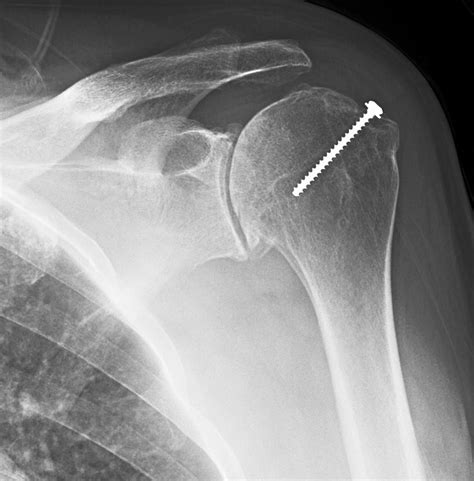

💡 Note: If you have had any previous shoulder surgeries involving metal hardware, such as pins, plates, or screws, let the technician know immediately, as this will be visible on the X-ray.

Managing Shoulder Pain Post-Diagnosis